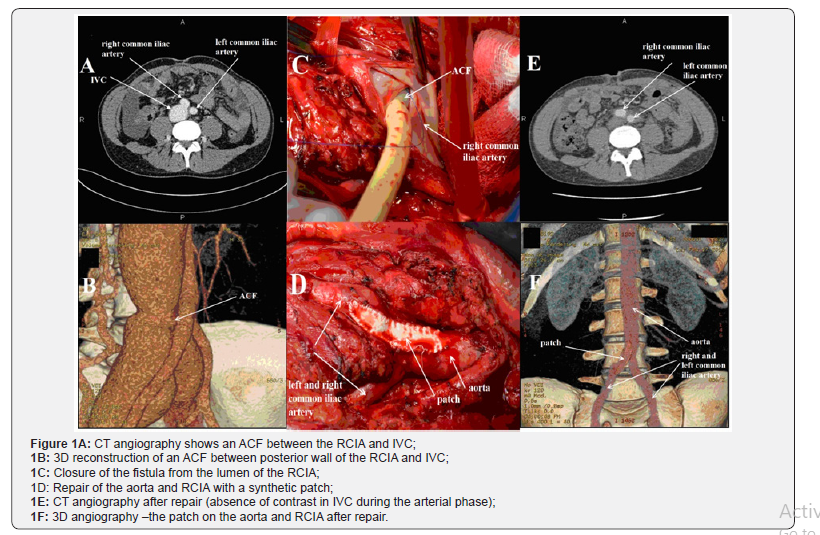

Abdominal drainage was performed with a daily evacuation of up to 1500ml. Cardiac MRI revealed no pathological signals or perfusion defects. Findings of abdominal CT, cytological examination of ascetic fluid, and fibro colonoscopy were all normal and that allowed us to exclude oncological causes of ascites. Bearing in mind the history of the abdominal stab wound, normal LVEF, and signs of heart failure, mainly due to the right heart, examination of IVC was recommended. An aorto-caval fistula (ACF) between the right common iliac artery (RCIA) and IVC was revealed by CT angiography (Figure 1A & 1B). The patient successfully underwent repair of his ACF with a synthetic patch to close the defect of aorta and RCIA (Figure 1C & 1D).

Echocardiography showed significant reduction of IVC (24mm), RV (38mm), tricuspid regurgitation (mild) and SPAP (34mmHg) within a week postoperatively. CT angiography did not reveal an ACF during the arterial contrast phase (Figure 1E). The patch was visualized on the anterolateral wall of the RCIA and aorta (Figure 1F).